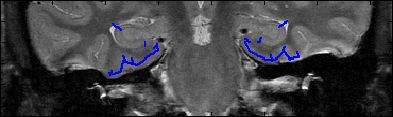

This is an example of one subjects demarcation. The A/P slice is slice

3.